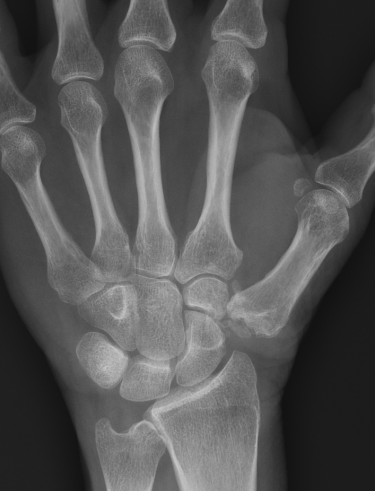

Eaton Classification

| Stage I | Stage II | Stage III | Stage IV |

|---|---|---|---|

|

Xray normal Synovitis |

Joint space narrowed Mild subluxation |

Severe joint space OA Radial subluxation of joint |

CMC + STT OA |

![]() |